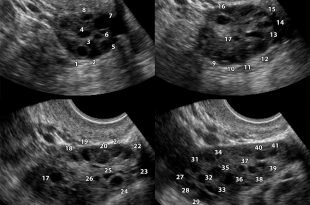

Болезни, поражающие печень, несут угрозу всему организму. Причины заболеваний железы — злоупотребление алкоголем или лекарствами, сбои в обменных процессах, инфицирование вирусами, огрехи в питании. Основные болезни — жировая дистрофия железы (гепатоз), воспаления органа различной этиологии (гепатиты), фиброзные и циррозные поражения с замещением паренхимы инертной ткань, дисфункция печени, рак. Клиника болезней скрытая, маскирующаяся под ухудшение общего состояния. Желтуха, боли справа в подреберье, тошнота говорят об усугублении процесса. В основе лечения — строгая диетотерапия, тщательный подбор гепапротекторов, отказ от вредных привычек.